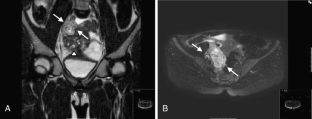

Isolated torsion of the fallopian tube is a rare medical emergency, especially in premenarchal girls. We present a 9-year-old girl with right-sided lower abdominal pain. Isolated torsion of the fallopian tube was suspected preoperatively because of the clinical presentation combined with the results of ultrasound and magnetic resonance imaging (MRI). At emergency laparoscopy, the isolated torsion of the fallopian tube could be reduced, and the tube could be salvaged. This case report shows that the use of ultrasonography and MRI or CT is a helpful diagnostic tool to recognize this condition at an early stage. Especially in young girls presenting with abdominal pain, this should be kept in mind, as digital vaginal examination and vaginal ultrasound most often cannot be used in the diagnostic process. In conclusion, because prompt surgical intervention is required to preserve the tube and prevent progression to peritonitis and possible detrimental effects on future fertility, isolated torsion of the fallopian tube should be considered in the differential diagnosis of lower abdominal pain in all female patients regardless of age.

Fig. 1

Fig. 2